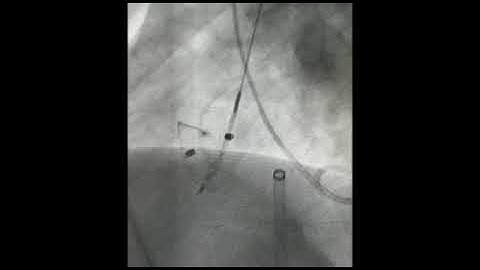

LV Angiogram profiling perimembranous VSD prior to closure with PDA occluder